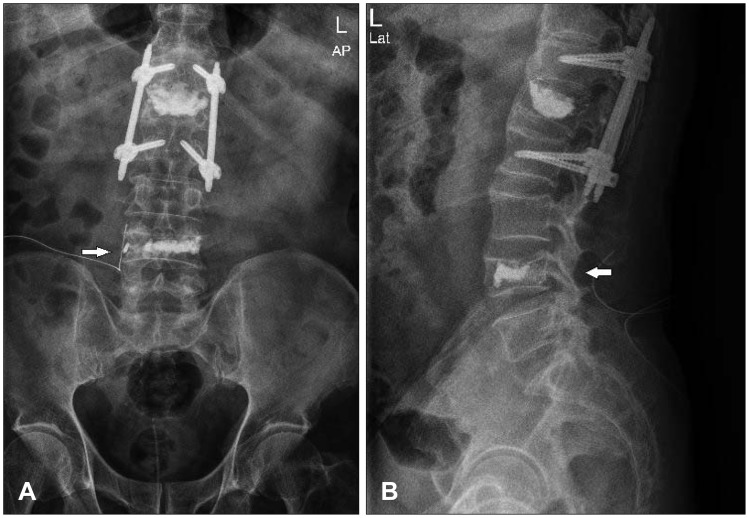

FIGURE 4.

Postoperative lumbar spine plain images, anterior-posterior (AP) view (A) and lateral view (B) show that the leaked bone cement along right L4 nerve root was disappeared.